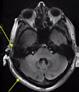

7 Tesla Neuroimaging Studies with the Tic-Tac-Toe Radiofrequency Coil System

Recently FDA-approved 7 Tesla (T) MRI can provide improved signal-to-noise ratio, resolution, and image contrast when compared with standard clinical MRI scanners (usually 1.5T or 3T). However, proton imaging at higher frequencies (~300MHz) and shorter wavelength (~13cm in brain tissues) can lead to inhomogeneities in the images and potentially cause high localized radiofrequency (RF) power deposition in the tissue. The Tic-Tac-Toe (TTT) RF coil system provides improved homogeneity and reduced power deposition. It is achieved thanks to an innovative coil design and a methodology of operation. Several clinical MRI sequences have been performed and compared with commercial RF coils, demonstrating the superior performance of the Tic-Tac-Toe RF coil system. Numerous clinical studies including NIH funded studies (~2,000 subjects) are currently being conducted using this coil at the University of Pittsburgh.

b) a) c) The Tic-Tac-Toe (TTT) radiofrequency head coil for 7T MRI Fig 1: in a), the implemented 16-channel TTT transmit RF coil; in b), the computational RF coil in c), the implemented RF coil with an 32-channel receive insert Fig. 2: The B1+ (magnetic field responsible for spin excitation) field homogeneity is highly degraded at 7T MRI due to a higher operational frequency (~297MHz). The TTT presents a more homogeneous field distribution when compared with the NOVA coil (a commercial coil) [1]. Measured Tic-Tac-Toe Measured Nova coil Regions with low B Simulated Tic-Tac-Toe B + maps in the brain: TTT vs NOVA RF coils TTT coil NOVA coil TTT coil NOVA coil Image comparison with the 32-channel NOVA commercial RF coil a) b) Fig. 3: In a), Turbo spin echo (TSE) sequence using the TTT coil with resolution of 0.4x0.4x2mm. In b), the same TSE sequence acquired with the commercial NOVA coil. In c), FLAIR sequence acquired with TTT coil with resolution of 0.7x0.7x2mm. In d), the same FLAIR sequence acquired with NOVA coil. The arrows point to regions of dark spots in the NOVA coil images and compare with similar regions on the TTT coil images [1]. c) d) High-resolution susceptibility weighted images showing cortical microvessels Fig 4 SWI images acquired at 0 2x0 2x1 5mm resolution In a) an axial slice of the whole brain image acquisition In b) and c), zoomed versions of a), detailing the micro-structures a) b) c) High resolution angiography without contrast agents 380μm a) b) Fig 5: Maximum intensity projection orientation and small vessels detectability isotropic image showing whole brain isotropic acquisition In d), 0 20mm are only detectable at higher resolution

Finger tapping task: activation of Functional MRI a) Diffusion MRI and fiber tracking Post-mortem a) a) b) Fig 7 In a), an structural MPRAGE image acquired at 0 75mm isotropic (skull removed using FSL package) In b), fiber tracking based on DTI acquisition, 64 directions, 1 5mm isotropic resolution The colors are defined for different orientations of the fibers Fig 8: In a), susceptibility weighted images acquired at 0 35mm isotropic, 32 min acquisition time, in a post-mortem brain fixated with formalin In b), a photograph of similar slice in the same brain Table 1: 7T MRI studies conducted at the RF Research Facility at University of Pittsburgh White matter legions (circle): Multiple Sclerosis study Stroke (circle): sickle cell disease study Automatic hippocampus segmentation: Midlife Neurocognitive Lacunar infarct (arrow): depression study White matter hyperintensities (arrows): Healthy Brain aging study (left) and Small Vessels disease in preclinical Alzheimer’s disease study (right) Fig 9: Sample of some studies listed in Table 1 using the developed 16 array (Fig a) There are 4 completed studies and 13 ongoing patient studies with approximated 2 000 patients scheduled FUTURE DIRECTIONS 64-channel Tic-Tac-Toe RF transmit coil for 7T MRI 0 Fig 10: In a), the 64-channel transmit coil computational modeling [2] To improve the field of view of the projector/monitor in fMRI studies, the frontal panels can be removed, resulting in a 56-channel coil In b), one assembled side of the coil In c), simulated B1+ field distribution: for an 8kW power amplifier capabilities (default in older 7T MRI scanners) a homogeneity (measured by the coefficient of variationCV) of 15 2% is achieved in the brain For an 16 kW power amplifier (available for the recently FDA approved Siemens 7T MAGNETOM Terra), an CV of 10 6% can be achieved in the brain 16 kW power amplifier: 8 kW power amplifier: a) b) c) max